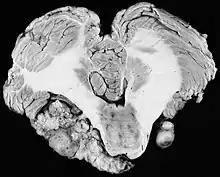

| Bilateral schwannomas in a patient with neurofibromatosis 2 | |

For the most part, unilateral sporadic vestibular schwannomas are readily treated successfully by modern medical techniques. Having bilateral VSs is a more troublesome condition. Bilateralism is considered to be the hallmark and main diagnostic criterion of Neurofibromatosis Type II (NF2), a genetic disorder that is heritable, progressive, difficult to manage, and has a 1 in 2 chance of being passed on to each offspring. NF2 patients tend to have a more severe mutation, although there are mild mosaic cases in which only some cells carry the mutation. Genetic testing confirming mutation of the NF2 gene is recommended. About 50% of people with NF2 have a de novo mutation, and about 50% of these new mutations will be mild mosaic cases which are less likely to be passed on. NF2 patients may develop other cranial and spine tumors. NF2 develops during the teens or early adulthood, whereas sporadic VSs are diagnosed mostly in patients between the ages of 40–60 years. Both varieties of VS (sporadic and NF2) are very rare, accounting for only about 8% of all primary brain tumors. The incidence of NF2 is approximately 1 per 60,000 people.[6][7][8]